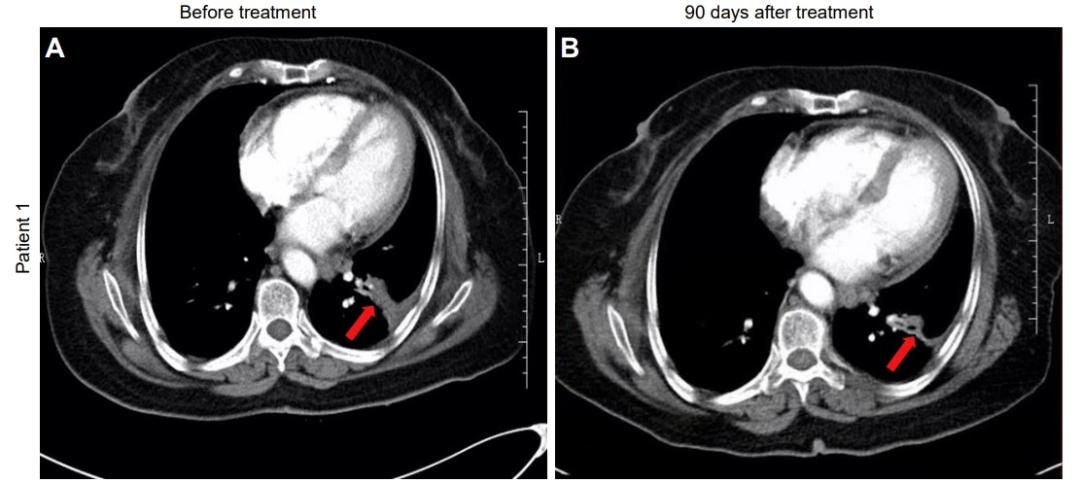

4、肿瘤显著缩小:在使用NK细胞+帕博利珠单抗联合治疗后,中位肿瘤最大横径(MTD)显著下降(P< 0.05)。值得一提的是,其中一位68岁的女性IVA期非小细胞肺癌患者,治疗前左肺下叶存在一个3.8 × 1.8 × 2.4 cm的片状肿瘤,治疗后第90天复查CT发现肿瘤显著缩小至2.5x1.2x2.1cm(详见下图)。

图片

▲图源“JCI”,版权归原作者所有,如无意中侵犯了知识产权,请联系我们删除

注:红色箭头表示肿瘤。